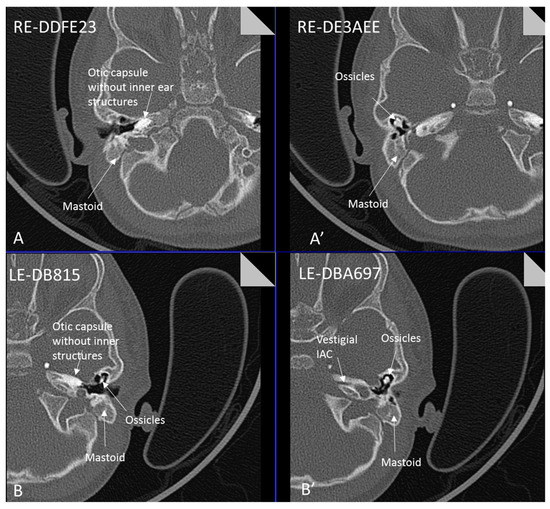

| Inner ear MRI features | Michels | Michels | Michels | L- otocyst rudimentary, R- Michel aplasia | Michels | L- Michel aplasia R- otocyst rudimentary | L- cystic vestibule R- cystic cochleovestibular malf | Michels, normal middle ear development | Michels | Michels | Michels | Michels | L- Michels R- rudimentarl cystic vestibule | Two subjects with rudimentary inner ear formation unilaterally | L- rudimentary vestibular structures R- Michels | Michels, normal middle ear development | Two subjects with cochlear basal turn, vestibule and posterior semi-circular canal | Michels, normal middle ear development | Middle ear involved. Hypoplasia petrous pyramids, bilateral labyrinth and IAC dysplasia. Stapes present in female. | CT Michels aplasia bilaterally Otic vesicle remnant ectopic in left mastoid | Michels; Middle ear structures involved | Michels | Michels |

| Inner ear (a)symmetry | S | S | S | A | S | A | A | S | S | S | S | S | A | A | A index | S | A n = 2 | S | S | S | S | S | A |